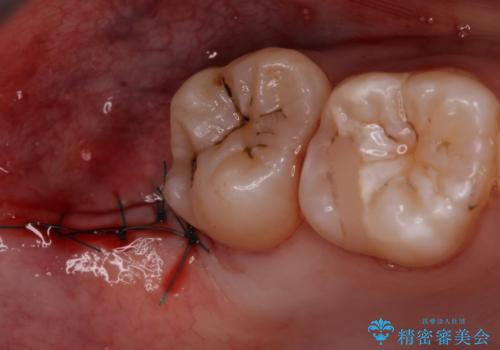

- 親知らず抜歯をご希望で来院されましたが、手前の歯が歯ぐきに覆われていたため抜歯と同時に歯ぐきの除去を行います。

今回は親知らずの抜歯と同時に周りの歯茎の除去を行いました。